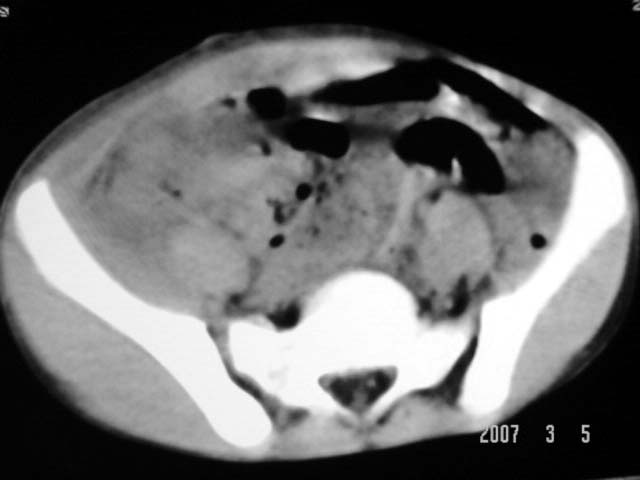

以下是引用dyqct在2007-3-5 10:28:00的发言:[br]右髂窝肿块。[br][br][br][br]